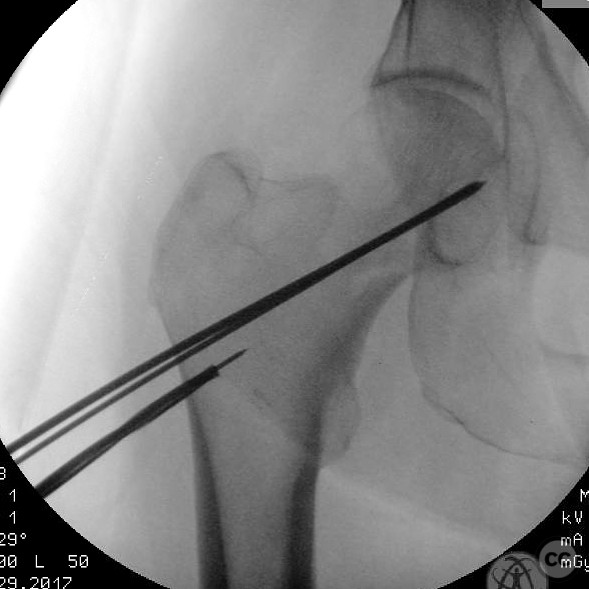

Patient positioning:  The patient was positioned supine on a fracture table to facilitate closed reduction and percutaneous fixation under fluoroscopic guidance.

Anatomical surgical approach:  A percutaneous approach was utilized, involving small stab incisions for the insertion of guide wires and cannulated screws. Fluoroscopic imaging was employed to ensure proper alignment and fixation.